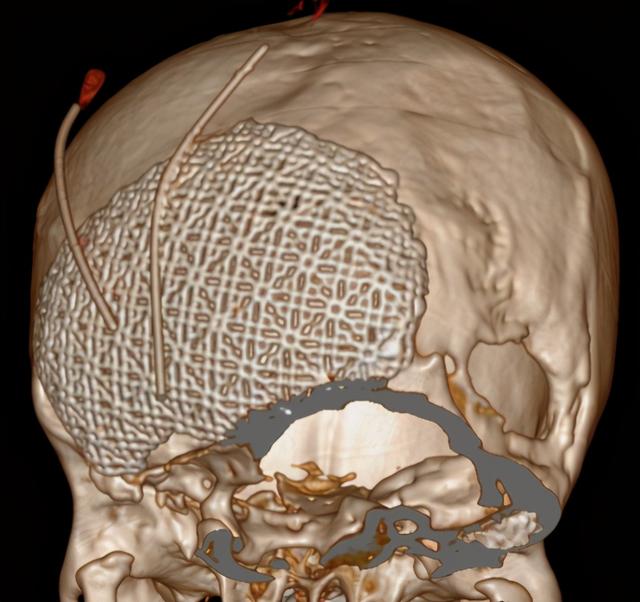

于是来到南昌市第三医院神经外科门诊,经过一系列的检查,头颅CT及MRI提示枕部存在一大一小颅骨缺损,其中大者达28*13cm,小脑萎缩明显,局部脑脊液充填,脑膜膨出伴少量脑膨出,要给如此巨大脑膜脑膨出行修补术,难度非常大,充分的术前检查、术前准备是必不可少的。

头颅MRV提示颅内静脉系统异常,窦汇、双侧横窦、乙状窦缺如,大量增生粗大引流静脉。头颅MRI未提示脑实质肿胀、梗塞、出血等表现。

术前颅骨缺损和计算机模拟修复模型

术后第二天头颅CT复查未见脑积水形成,无异常出血。头颅CT三维重建提示颅骨缺损修补贴合良好。